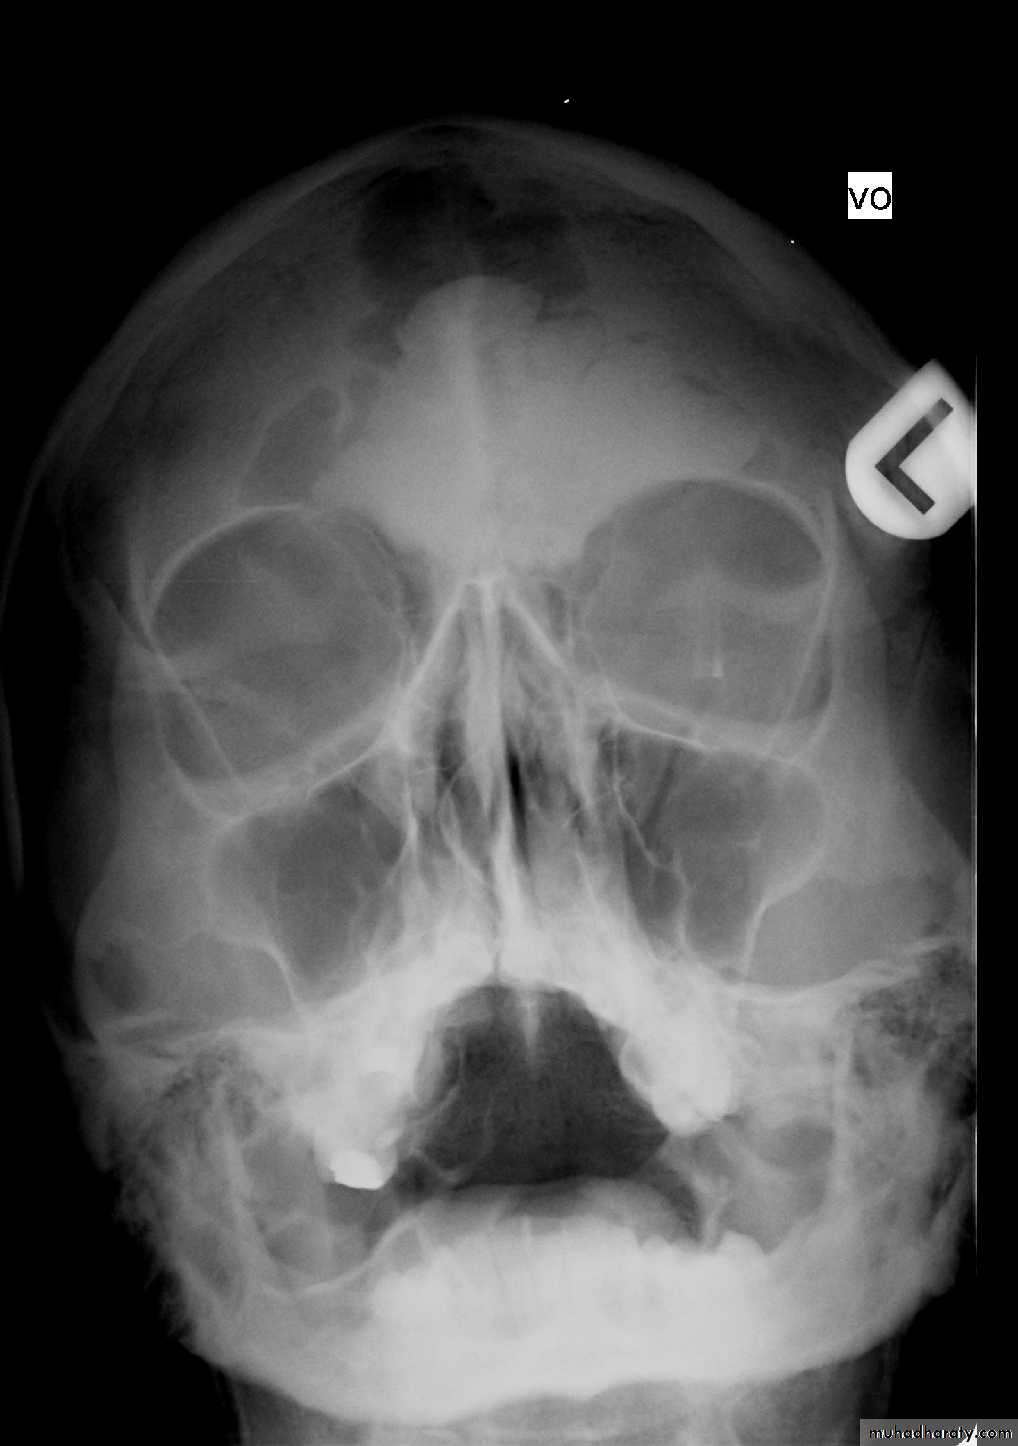

DIAGNOSIS:X-ray PNS.

CT Scan of PNS ( Coronal & Axial).

Biopsy - Nasal Mass / Endoscopic.